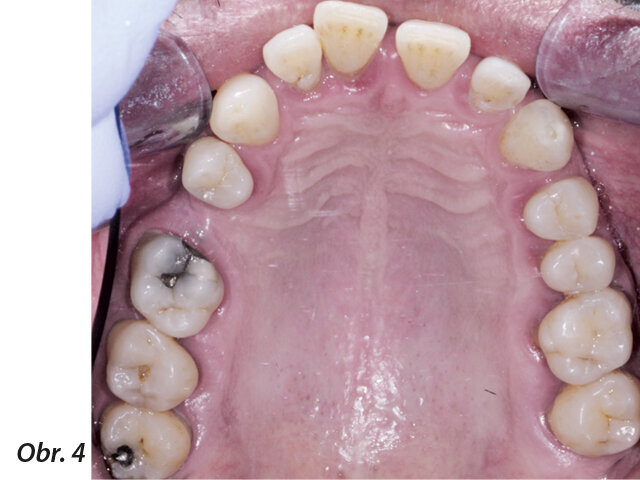

Obr. 1–5: Fotografi cká dokumentace počátečního stavu před parodontologickým ošetřením

49letý pacient přišel na naše oddělení se stížností na krvácení dásní a rozestupování frontálních zubů (obr. 1–5).